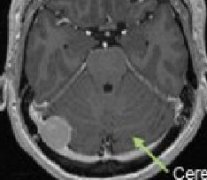

小脑脑桥脑膜瘤手术风险大吗?小脑脑桥角是颅内脑膜瘤多发部位之一,约占颅内脑膜瘤的10%左右,肿瘤的基底附着于乙状窦、岩上窦、岩下窦或颈内静脉孔附近。其部位贴近小脑幕,...